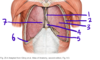

What are the 3 concentric layers of hypaxial muscles, as they present in the thorax?

Which direction do they go?

External intercostal muscles \//

Internal intercostal muscles //\

Transversus muscles (innermost intercostal + transversus thoracis) //\ (similar to intercostal muscles)

Note: Transversus thoracis is deep to the innermost intercostal muscles

What are the relevant components of the intercostal space?

Boundaries: upper and lower rib

3 concentric layers of muscle (external, internal, innermost)

Each space is associate with a neuromuscular bundle (intercostal nerve, vein, artery)